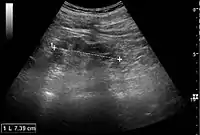

Kidney ultrasonography is useful for diagnostic and prognostic purposes in chronic kidney disease. Whether the underlying pathologic change is glomerular sclerosis, tubular atrophy, interstitial fibrosis, or inflammation, the result is often increased echogenicity of the cortex. The echogenicity of the kidney should be related to the echogenicity of either the liver or the spleen (Figure 22 and Figure 23). Moreover, decreased kidney size and cortical thinning are also often seen and especially when disease progresses (Figure 24 and Figure 25). However, kidney size correlates to height, and short persons tend to have small kidneys; thus, kidney size as the only parameter is not reliable.[54]

Nephrotic syndrome. Hyperechoic kidney without demarcation of cortex and medulla.[54]